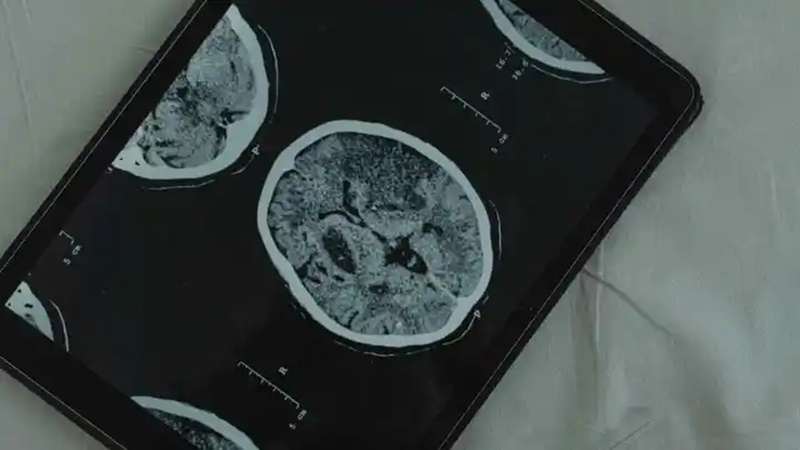

To get to the bottom of this, scientists from Duke, Harvard, and the University of Otago have unveiled a game-changing tool called DunedinPACNI. It uses a single AI brain scan to reveal how fast a person is biologically aging. It’s changing the way we track aging and the long-term health risks associated with it.

The DunedinPACNI was named after the Dunedin Study, which followed over 1,000 people since their birth in the 1970s. Researchers analyzed decades of data, looking at factors like blood pressure, BMI, cholesterol, glucose, kidney function, and even dental health, to come up with a unique “aging score” for each participant. The new MRI-based AI brain scan can predict this score with surprising accuracy from a scan taken at age 45.

DunedinPACNI is the future of preventative healthcare

The team believes DunedinPACNI could change the landscape of preventive medicine. If it were possible to spot health risks early through an AI brain scan, at-risk individuals might be motivated to make healthier lifestyle changes (e.g., diet, exercise, and stress management). It could also help healthcare providers evaluate the effectiveness of treatment and slow the progression of age-related diseases.

The DunedinPACNI is a great tool that offers a non-invasive and powerful window into biological aging that traditional blood tests never could. A single AI brain scan provides a lifetime of health insights. It comes at a much-needed time as chronic diseases are on the rise. It may just be one of the key ingredients in predicting health outcomes and coming up with personalized wellness strategies.